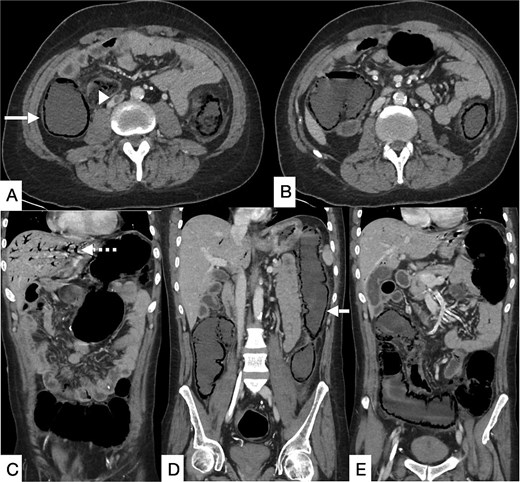

Contrast-enhanced computed tomography (CT) of the abdomen demonstrated long-segment ischemia extending from the transverse to descending colon, characterized by wall thickening, mucosal hypoenhancement, and pericolic fat stranding. A non-occlusive thrombus was noted in the IVC (Fig. 1). Review of prior CT angiography, performed several months earlier for gastrointestinal bleeding, had shown features of colonic angiodysplasia, including mucosal hyperenhancement, early venous filling, and serpiginous submucosal vessels (Fig. 2).

Selected CT angiogram of the abdomen and pelvis in axial (A) and coronal (B) planes showing mild diffuse thickening and mucosal hyper-enhancement of the descending colon, with prominent feeding mesenteric arteries and early draining vein dilation, consistent with angiodysplasia.